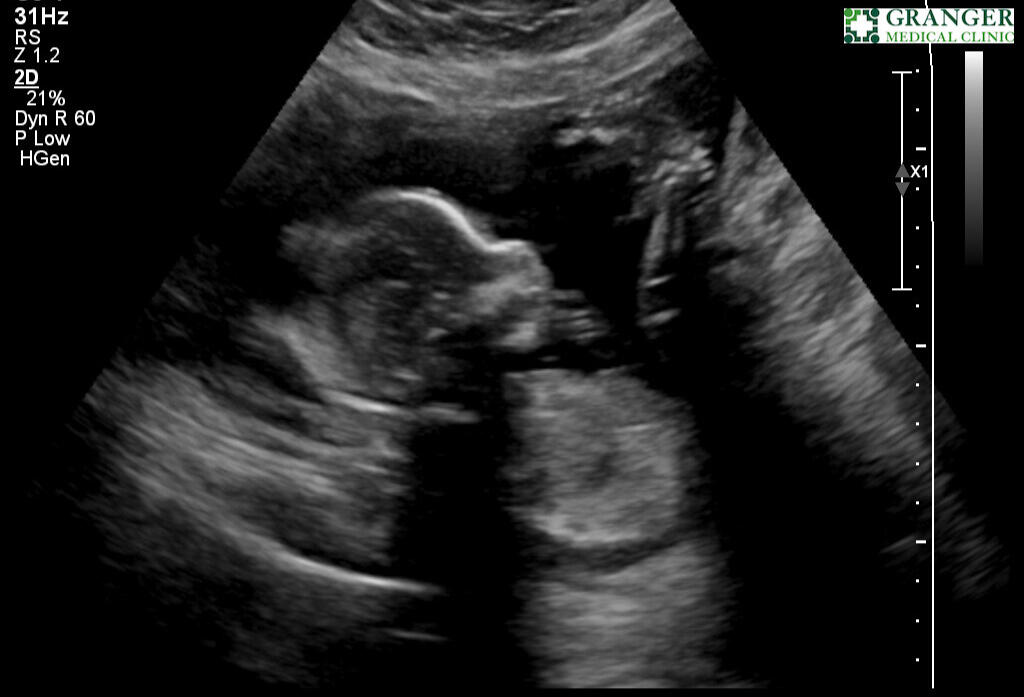

Ultra sound @ March 25th

It has only been three months and three weeks since we found out we are having a child.Since then, we have gained a bassinet in our bedroom and a closet filled with new baby clothing. New artwork for our nursery and overall has been the subject of conversation every single day since.It is sufficient to say that our lives have changed forever.Having this drastic a change in such a short time has come with much stress and complications, and almost all aspects of our lives.Most surprising are the emotional changes we have undergone over the past three months. As it turns out, (from parenting books and colleagues’) husbands and wives will go through drastic hormonal changes while the wife is pregnant.All this has led to a lot of planning for our future baby. There are times when I feel more stress than I've ever felt in my entire life.However, in the same breath, I believe I have also felt the most gratitude and love for my family that I have ever felt.For sure, things are differentBut overall, despite all the sleepless nights and worrying about our baby’s future, I’ve been able to see the world in a different, more positive light than ever before.Abree and I have been dreaming of this moment and have been planning for our new child. Now that it is here, it feels almost surrealWe are very excited